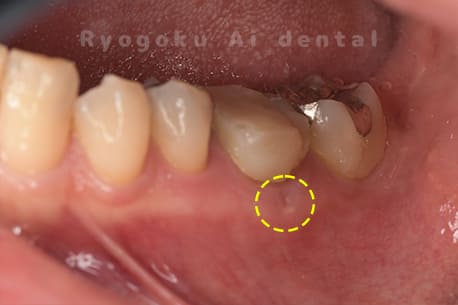

Case05

-

- 原因

- 慢性根尖性歯周炎

- 治療内容

- マイクロエンド

- 治療費用

- 121,000円(被せ物は含まない)

他院ではお薬の交換と抗生剤の処方で経過を診ていた患者さんです。歯茎の腫れが治らないとのことで、根管治療を開始し、2回目のご来院で腫れが引いたケースです。現在は被せ物も入り、良好に経過しております。

<リスク・副作用>

術後は痛み、腫れ、痺れなどの副作用が生じる場合があります。症状が再発する可能性があります。